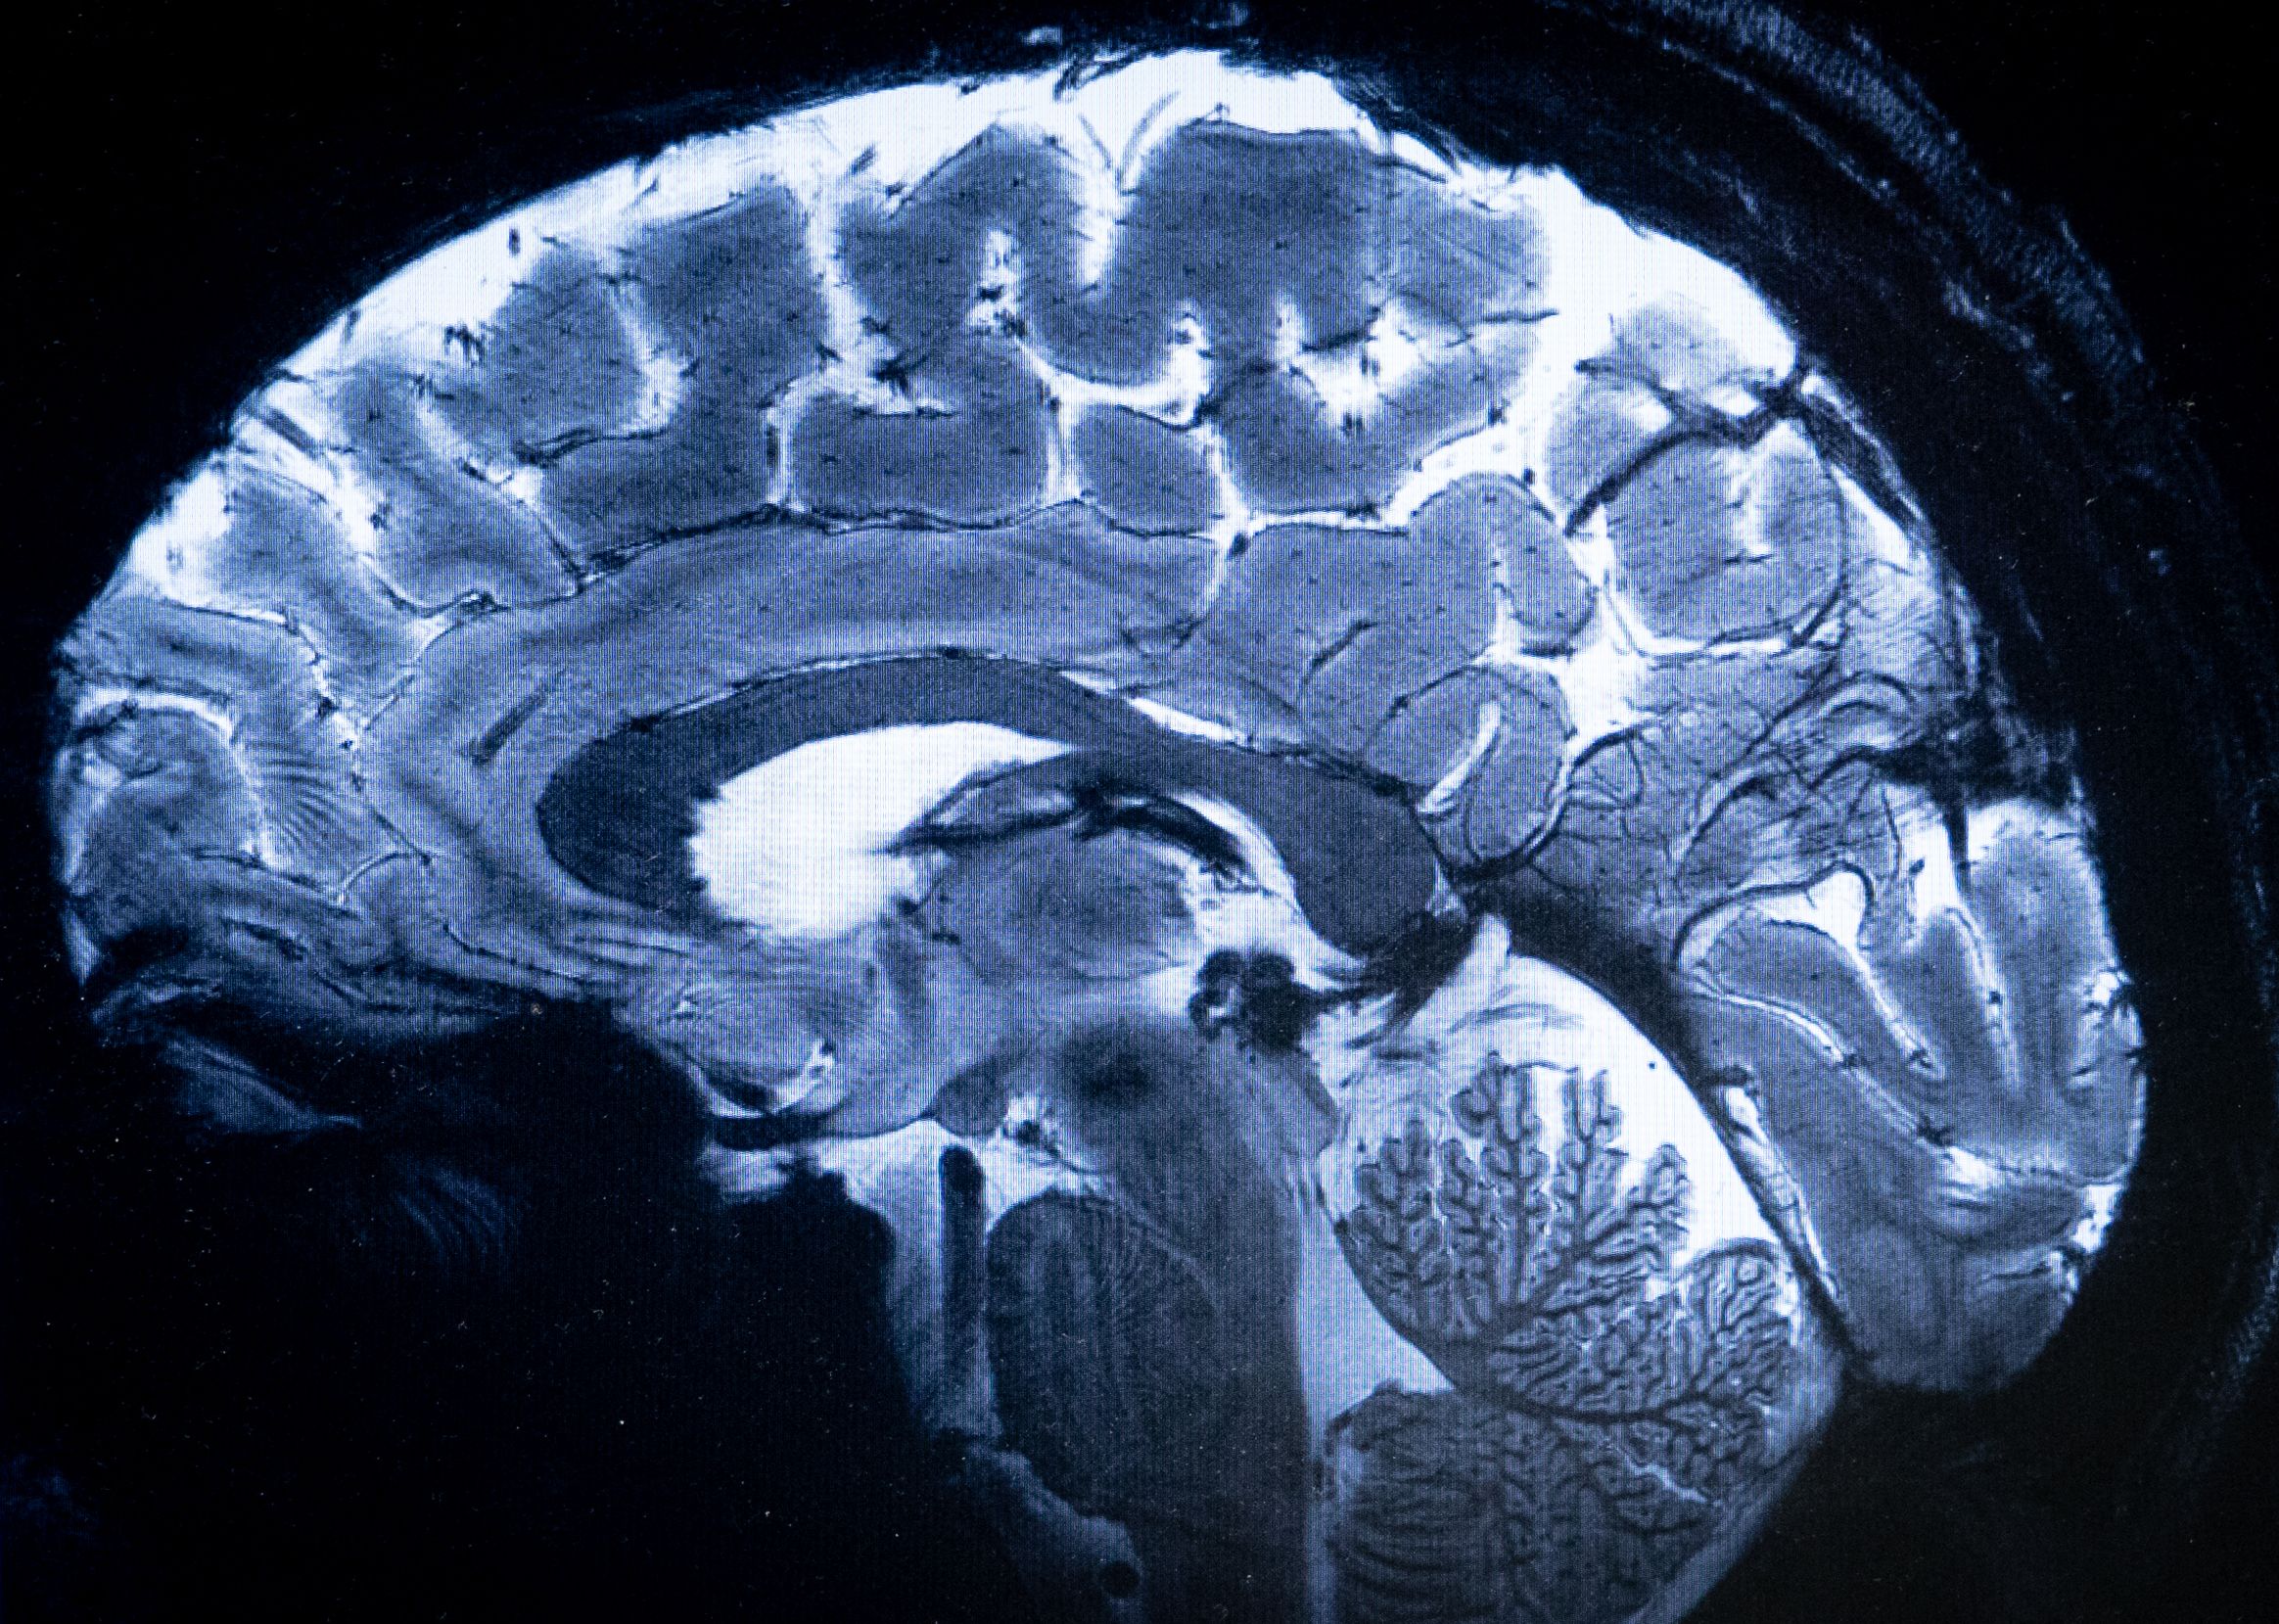

ويصل المجال المغناطيسي لهذا المغناطيس الاستثنائي إلى 11,7 تيسلا، مما يتيح الحصول على صور أكثر دقة بعشر مرات من تلك المنتجة حاليا في المستشفيات، حيث لا تتجاوز قوة التصوير بالرنين المغناطيسي 3 تيسلا.

وعلى شاشة ألكسندر فينيو تتم مقارنة الصور المقطعية للدماغ بما كان ليوفره تصوير بالرنين المغناطيسي بقوة 3 أو 7 تيسلا. وقال فينيو "باستخدام هذا الجهاز، يمكننا رؤية الأوعية الصغيرة جداً التي تغذي القشرة الدماغية، أو تفاصيل المخيخ التي كانت غير ظاهرة تقريباً حتى الآن".